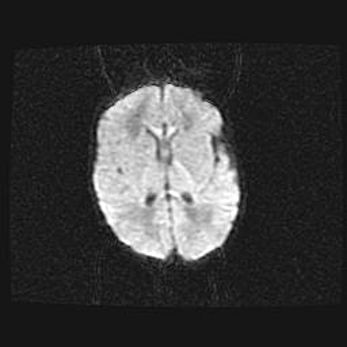

Наружная гидроцефалия с возможной атрофией височных областей.

Возраст: 28 дней

Вес: 3670 г

Пол: мужской

Окружность головы: 38 см

Срок гестации: 40 недель

Гидроцефалия головного мозга у новорожденных – это заболевание, которое характеризуется скоплением избыточного количества спинномозговой жидкости в желудочковой системе головного мозга в результате затруднения её перемещения от места выработки к месту поглощения в кровеносную систему или вследствие нарушения абсорбции. При открытой наружной форме гидроцефалии у новорожденных расширяются и переполняются субарахноидные пространства.

При нормотензивных  формах,  которые,  как  правило,  являются  следствием  перенесенных ишемических  повреждений  паренхимы  мозга,  возможно  сочетание микроцефалии  с нормотензивной гидроцефалией. В основе данных изменений лежит атрофия больших полушарий с преимущественной  локализацией  в  лобно-височных  областях.